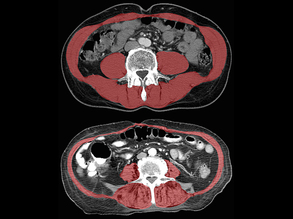

Core Condition